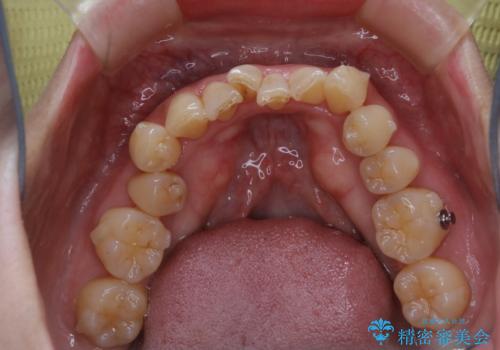

- インビザラインでのマウスピース矯正中に、歯の黄ばみが気になるため綺麗に白くしたいとのことでした。PMTC60分コースを行いました。

PMTC(保険外治療)は、毎日の歯磨きで落としきれない汚れや、コーヒ、紅茶・タバコのヤニなどの着色も除去します。目には見えない歯と歯の間・歯肉の境目・インビザライン中はアタッチメント周囲などに残っているプラーク(歯垢)もしっかり取り除きます。PMTCでは専門的な機械や材料を使用して、徹底的に汚れを除去するため、虫歯・歯周病・口臭予防などにつながります。